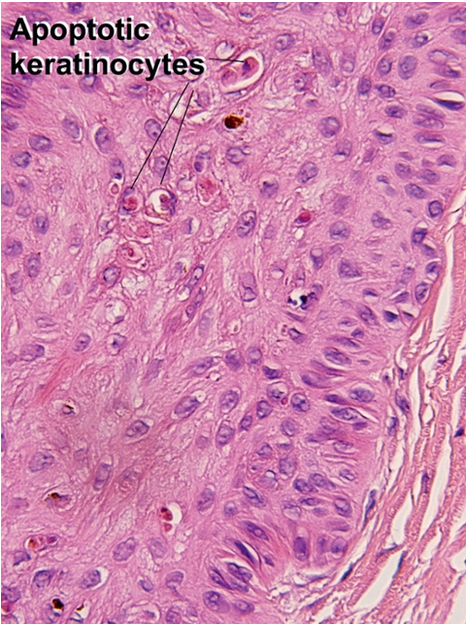

Apoptosis

“dead red” keratinocytes with pyknotic nuclei